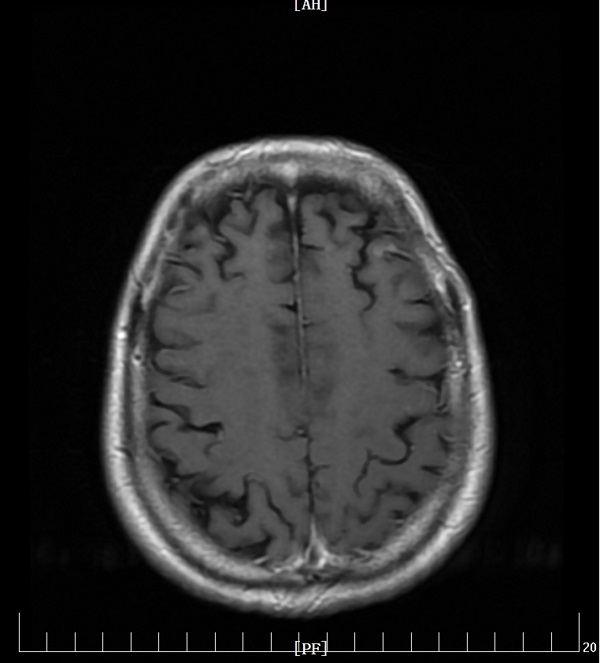

充分研究病情后,刘娟妮主任团队积极与家属沟通,对症治疗的同时,在CT引导下行经皮肺穿刺活检术,术后病理提示:中分化腺癌,基因检测结果提示:EGFR Exon19突变。明确诊断后,刘娟妮主任团队一边安慰患者及家属的情绪,一边对患者的全身状况及疾病进行了充分的评估,邀请相关科室会诊,经MDT讨论并结合患者目前症状、基因检测结果分析及国内外最新指南推荐,制定了个性化的治疗方案,给予口服三代靶向药控制肿瘤。治疗1个月后,复查头颅MRI及胸部CT,结果显示患者肺原发肿瘤、脑多发转移瘤较前均缩小、部分消失。

治疗前

治疗后